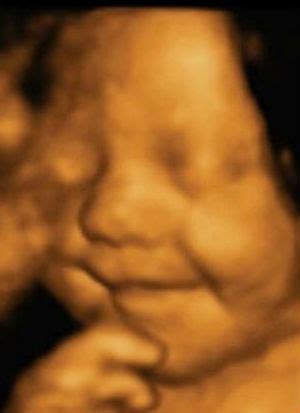

Pastaruosius kelerius metus plačiai kalbama apie 3D ir net 4D vaisiaus echoskopiją. Paklausta, ką reiškia šie skaičiai, gydytoja paaiškina: „2D - tai įprasta dvimatė echoskopija, kai ultragarso aparato ekrane ar pateiktoje nuotraukoje matomas nespalvotas dvimatis vaizdas. 3D jau leidžia sudaryti erdvinį trimatį vaizdą, kai ekrane galima stebėti ir vaisiaus veido bruožus, 4D - tai iš kelių atskirų 3D vaizdų sudarytas vienas klipas, tarsi filmukas.

Viso vaikelio nuotrauka ir video nėštumo pradžioje (18-20 sav.) 3D / 4D echoskopu matyti, kaip vaisius spardosi - jis jau gali vartytis, judinti kojytes, rankytes, pirštukais liesti veidą, juos čiulpti. Vaikelio veiduko nuotraukos nėštumo pabaigoje (26-32 sav.) 3D ultragarso tyrimu yra aiškiai matomi realūs vaikelio veido bruožai, daromos 3D nuotraukos ir video įrašai. Tokie pasimatymai sukelia mamai ir šeimos nariams ypatingą artumo ir susipažinimo jausmą.